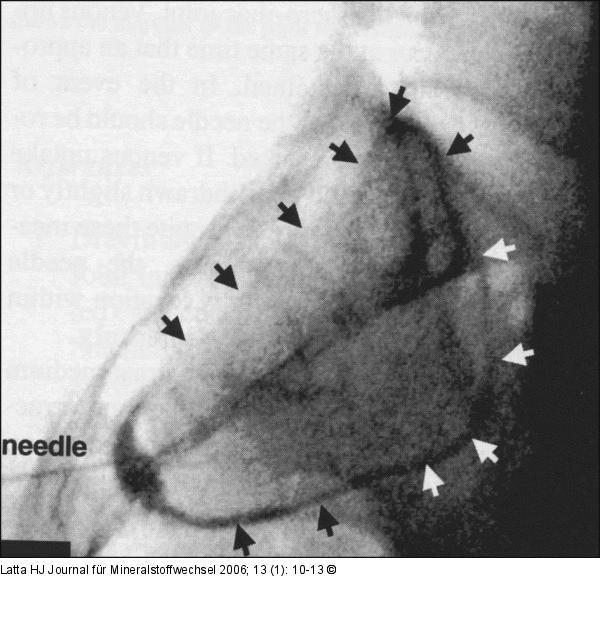

Abbildung 3a-b: Ileosakralgelenk Intraartikuläre Darstellung des linken Ileosakralgelenkes mit KM in zwei Ebenen. |

Abbildung 3a

Abbildung 3a-b: Ileosakralgelenk

Intraartikuläre Darstellung des linken Ileosakralgelenkes mit KM in zwei Ebenen. |